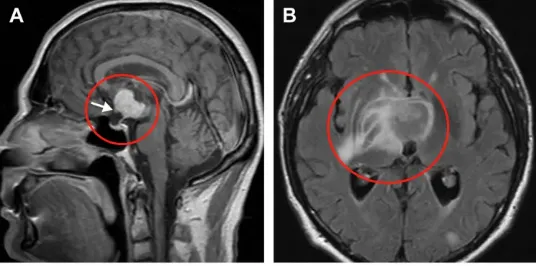

术前鞍上增强MRI显示,肿瘤延伸至第三脑室,有实性成分(a)。视神经交叉向前移位(箭头)。垂体和蝶鞍似乎正常。由于T2病灶周围水肿和反转恢复图像液体衰减并右侧基底神经节外侧延伸,怀疑下丘脑侵犯(B)。

李先生的MRI检查显示,其肿瘤不仅占据鞍上区,还向上延伸至第三脑室,且包含实性成分;更令人担忧的是,影像学提示肿瘤已侵犯下丘脑,T2序列可见右侧基底神经节外侧存在水肿信号。视神经交叉被肿瘤推向前方。